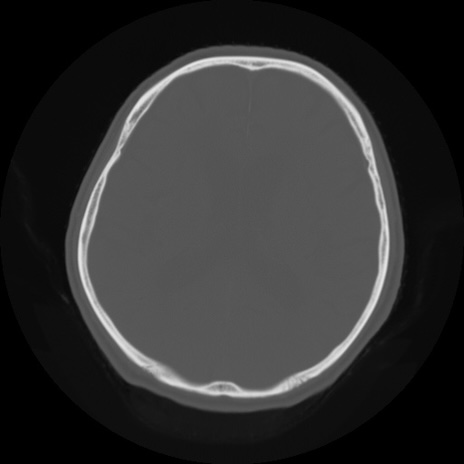

【頭部】症例5 CT(横断像)

症例5の画像所見と診断は?

CT(冠状断像)